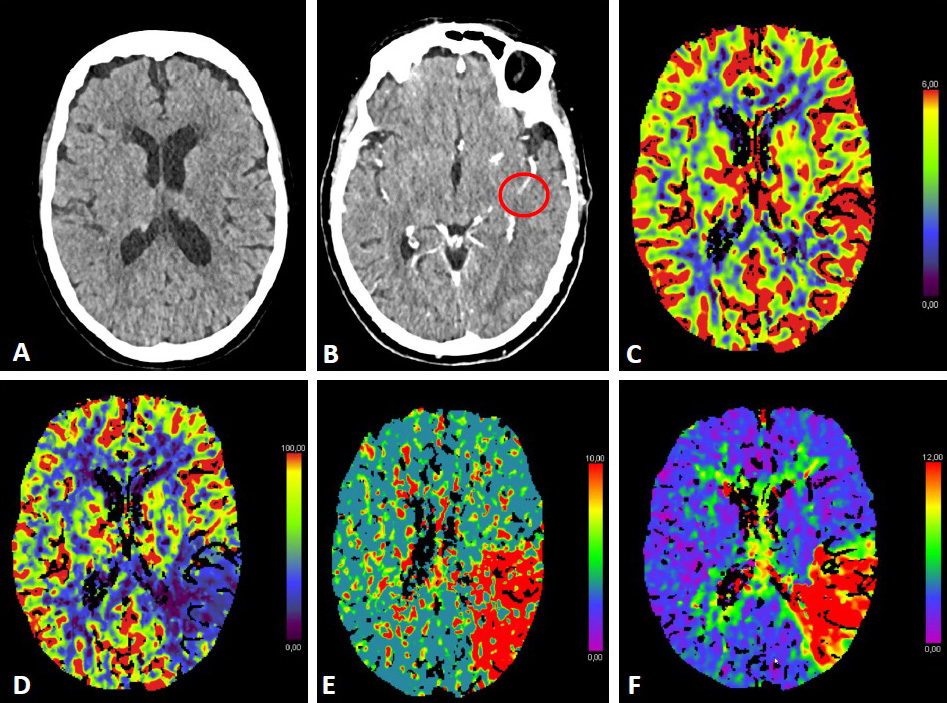

Within the 6-hour time window, the selection of patients with anterior

circulation stroke eligible for MT is based on non-contrast computed tomography

(NCCT) or magnetic resonance imaging (MRI), including angiography (CT-A or MR-A).

The Alberta Stroke Program Early CT Score (ASPECTS, based on NCCT) estimates the

amount of infarcted brain parenchyma in the MCA territory (Fig. 1) [29]. Overall,

a beneficial effect of MT can be expected in patients with ASPECTS

Fig. 1.ASPECTS. Visualization of the ASPECTS territories (A,B). The following areas are covered: M1 (anterior MCA cortex, frontal operculum), M2 (anterior temporal lobe, laterally to the insula), M3 (posterior temporal lobe, posterior MCA cortex), M4 (anterior MCA cortex superior to M1), M5 (lateral MCA cortex superior to M2), M6 (posterior MCA cortex superior to M3), insula (I), internal capsule (IC), caudate (C), and lentiforme nucleus (L). Each area accounts for 1 point. The maximum ASPECTS score is 10. Hypodensity in a described area leads to a deduction of one point. (C,D) show an example of CT ASPECTS. Hypodensity in the M2 and M6 areas is observed. Total ASPECTS: 8.